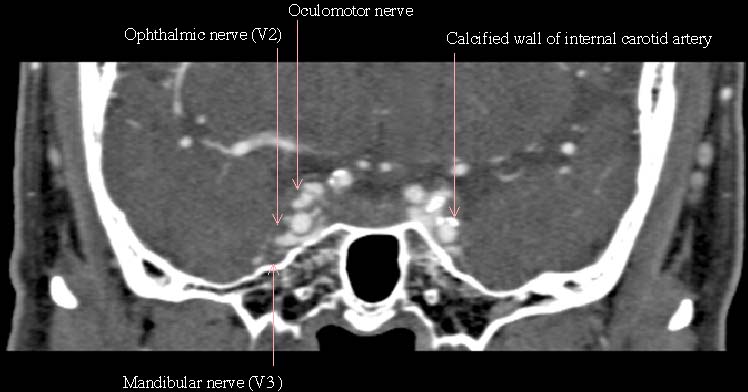

0.5mmx4, Pitch 3.0, 60mm, 20 seconds, 150mAs